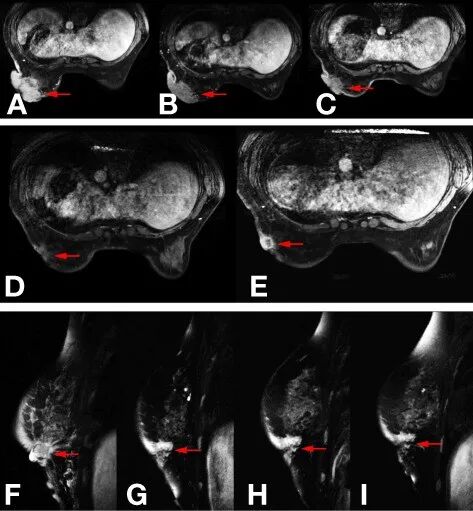

患者身体健康,无高血压、糖尿病病史,无吸烟、饮酒等不良嗜好。13岁初潮,末次月经2017年10月11日。在治疗开始之前,研究者对该患者进行了全面的检查,并排除了任何远处转移。根据第7版美国癌症联合委员会(AJCC)分期手册,临床分期为cT4N2aM0。由于当时帕妥珠单抗和T-DM1尚未在中国获批,在获得知情同意后,研究者根据美国国家综合癌症网络(NCCN)指南采用了TCbH方案(多西他赛,75mg/m2d1;卡铂,AUC=6d1;曲妥珠单抗,第1周期8mg/kg,此后6mg/kgd1),21天/周期作为一线治疗。5个周期后(2017年11月6日-2018年1月30日)复查乳腺MRI(图1B):肿块大小由91mm×55mm×87mm缩小至84mm×48mm×72mm,根据实体瘤疗效评价标准(RECIST 1.1版)评价标准,研究者将治疗效果判断为疾病稳定(SD)。

基于NOAH试验,联合应用曲妥珠单抗和蒽环类药物的有限周期有效,心脏毒性可控。因此,研究者选择ECH(表柔比星,90mg/m2d1;环磷酰胺,600mg/m2d1;曲妥珠单抗,6mg/kgd1,21天/周期)方案作为二线治疗(2018年2月27日-2018年5月23日)。4个周期后复查乳腺MRI(图1C)示:肿瘤由84mm×48mm×72mm缩小至66mm×29mm×56mm,按RECISTv1.1评价标准,治疗效果仍为SD。由于疗效仍未达到PR,因此将方案改为白蛋白结合型紫杉醇联合曲妥珠单抗。对于既往接受过紫杉烷类治疗的转移性乳腺癌患者,白蛋白结合型紫杉醇+曲妥珠单抗的客观缓解率仍为54.2%,在GBG69试验中,白蛋白结合型紫杉醇+曲妥珠单抗(EC)作为新辅助治疗优于紫杉烷联合曲妥珠单抗(EC)。因此,研究者选择白蛋白结合型紫杉醇联合曲妥珠单抗作为三线治疗(白蛋白结合型紫杉醇,125mg/m2d1,d8;曲妥珠单抗,6mg/kgd1,21天/周期)。患者在前两个周期后获得PR(图1D),但两个周期后,疗效恶化至疾病进展(PD)(图1E)。由于患者在三线基于曲妥珠单抗的治疗方案后出现获得性曲妥珠单抗耐药,因此需要另一种具有不同抗HER2治疗机制的治疗方案。为研究耐药的潜在原因,采用肿瘤再穿刺的组织进行425个基因panel的新一代基因测序(NGS)。根据NGS报告,检测到ERBB2、CDK12和MYC扩增持续存在,丰度分别为15.7、16.2和7.6。同时,IDH1基因上存在p.R314H突变,TP53基因上存在p.H179R突变。ERBB2基因上,患者有L755S和K907R突变。L755S突变表明对曲妥珠单抗和拉帕替尼耐药,可能对来那替尼敏感,这是一种不可逆的pan-HERTKI。当时,来那替尼还没有进入中国,一个类似的药剂吡咯替尼刚刚获得国家食品药品监督管理总局(NMPA)的批准,其II期试验已经表明,用于治疗晚期HER2阳性乳腺癌患者,吡咯替尼联合卡培他滨的疗效优于拉帕替尼联合卡培他滨。因此,研究者选择吡咯替尼加卡培他滨(吡咯替尼,400mg/日d1—21;卡培他滨,1250mg/m2bidd1—14,21天/周期)作为四线治疗方案。6个周期后(2018年8月28日-2018年12月29日),患者达到PR(图1F-I),乳房表面几乎完全愈合。患者于2019年1月16日行左乳腺癌乳房切除局部旋转皮瓣移植术,术后病理报告:浸润性导管癌,Miller—Payne分级4级改变,肿瘤大小1.0cm×0.8cm×0.8cm,淋巴结阴性(0/14)。免疫组化提示ER(-)、PR(-)、C-erbb-2(+++)、ki-67(70%+)。患者继续接受吡咯替尼联合卡培他滨(吡咯替尼,400mg/天d1–21;卡培他滨,1,250mg/m2bidd1–14,21天/周期)同步放疗(左胸壁加左锁骨上区,5000cGy/25f),吡咯替尼联合卡培他滨继续给药1年。吡咯替尼加卡培他滨辅助治疗1年后总体检查无转移或复发征象。患者因重度手足综合征暂停卡培他滨治疗,并服用吡咯替尼单药再治疗1年(表1),第二次(2019年6月)和末次定期随访(2021年3月)显示无转移或复发体征。